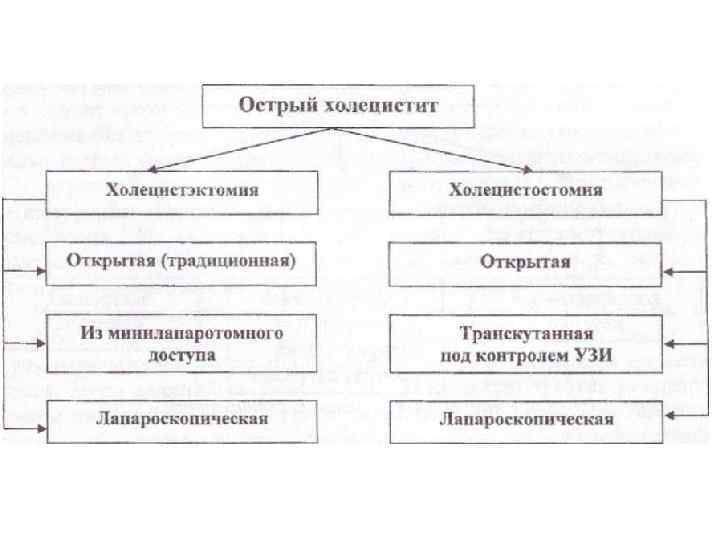

Жедел холецистит кезіндегі операциялар ауырудың басталған уақытына тәуелді. Жедел операция- жайылған перитонит кезінде операция алды дайындықсыз жасалады. Ерте Кейінге қалдырған операция- алғашқы 24 сағат ішінде консервативті ем мен бақылау фонында симтоматика сақталса немесе ауыру өршісе. Кеш Кейінге қалдырған операция- 24 -48 сағат аралығында жасалады. Оң жақ қабырға астында әлсіз ауырсыну болса және УЗИ мәліметі бойынша. Жоспарлы операция- консервативті емнің эффективтілігінде және ұстамаларды басу үшін.

Дәстүрлі холецистоэктомия

Кіші жолмен жасалатын холецистоэктомия Көрсеткіштері: - жедел калькулезді холецистит - холецистолитиаз, холедохолитиаз, кеңеймеген; -ЛХЭ кезіндегі техникалық қиыншылықтар. Қарсы көрсеткіштер: - іш қуысы ағзаларын интраоперационды ревизия жасау қажеттілігі; - Жайылған перитонит.

Лапароскопиялық холецистоэктомия Көрсеткіші: жедел холецистит (егер операцияны ауыру басталғаннан 48 сағат аралығында жасаса). Қарсы көрсеткіштері: айқын жүрек-өкпелік жеткіліксіздік; емге көнбейтін қан ұю бұзылыстары; жайылған перитонит; іштің алдыңғы қабырғасының қабыну өзгерістері; жүктілік (II-III триместр); семіздік III-IV степень; ауыру басталғаннан 48 сағаттан кейін; механикалық сарғаю; іш қуысының жоғарғы этажында бұрын болған операциялар кезінде.

УЗИ бақылауымен транскутанды холецистостомия Қарсы көрсеткіштері: перитонит, гангренозды холецистит, «фарфоровый» холецистит

Ашық холецистостомия

Лапароскопиялық холецистостомия